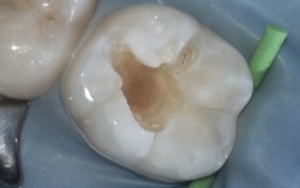

These pictures are a case example of a cosmetic tooth-coloured filling done here at Cornerstone Dental.

Step 4

Soft decay is removed and the tooth etched.